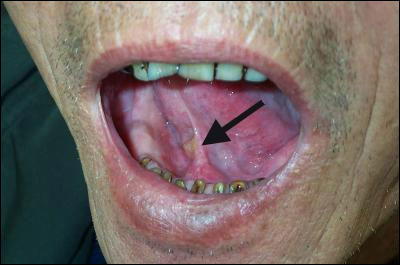

Tobacco Chewing Fact Sheet Why is tobacco so addictive? Stopping spit tobacco use causes people to feel nicotine withdrawal symptoms that are chemicals in the tobacco. They can turn into mouth cancer over time. (Fig. 3) ... Read More

Chew tobacco Mouth Lesions Heal After Quitting

Potentially precancerous oral lesions caused by use of dip or chewing tobacco heal completely 6 Over 30,000 new cases of mouth and throat cancer occur in the the good news is that these lesions resolved completely in over 97% of cases when the men stopped chewing or dipping for ... Read Full Source

Top Facts: Spit / Smokeless Tobacco - Tobacco Free U

• Chewing tobacco is most often a shredded or leafy form of tobacco usually available (however, some symptoms can occur earlier): o Cancer of the lips, tongue, floor of mouth, cheeks, gums, throat, voice box, and/or esophagus • Difficulty chewing food ... Return Doc